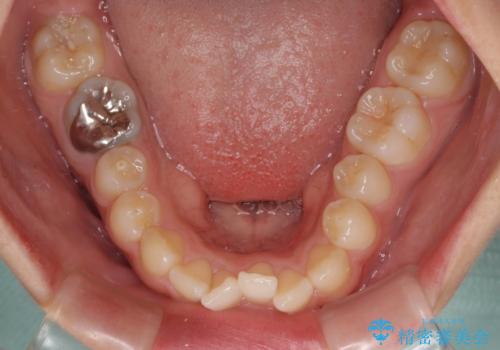

- 前歯のクロスバイトと口元の膨らんだ横顔の印象を気にして来院された患者様です。

しかしながら、唇を閉じたときに口元に緊張感があり、そのまま叢生を解消すると横顔が突出した印象になる可能性が高かったため、上下左右の小臼歯4本を抜歯して、ワイヤー装置にて矯正治療を行うこととしました。

矯正治療後には、目立っていた奥歯の銀歯をオールセラミッククラウンへ作り替え、スッキリした口元に仕上がりました。